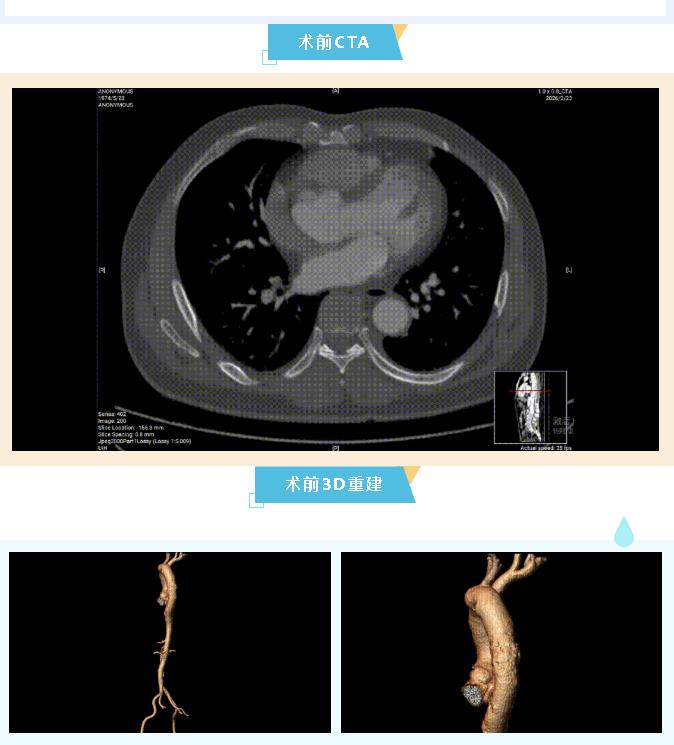

该患者主动脉弓部扩张,扩张起始处位于左颈总动脉(LCCA)后缘;降主动脉扩张,扩张起始处距左锁骨下动脉(LSA)后缘4mm(小弯侧);扩张末端距头臂干(IA)后缘180mm(大弯侧);右椎优势。

患者:男性,54岁

主诉:突发胸痛两天,加重一天

术前诊断:主动脉弓部扩张

术前CTA